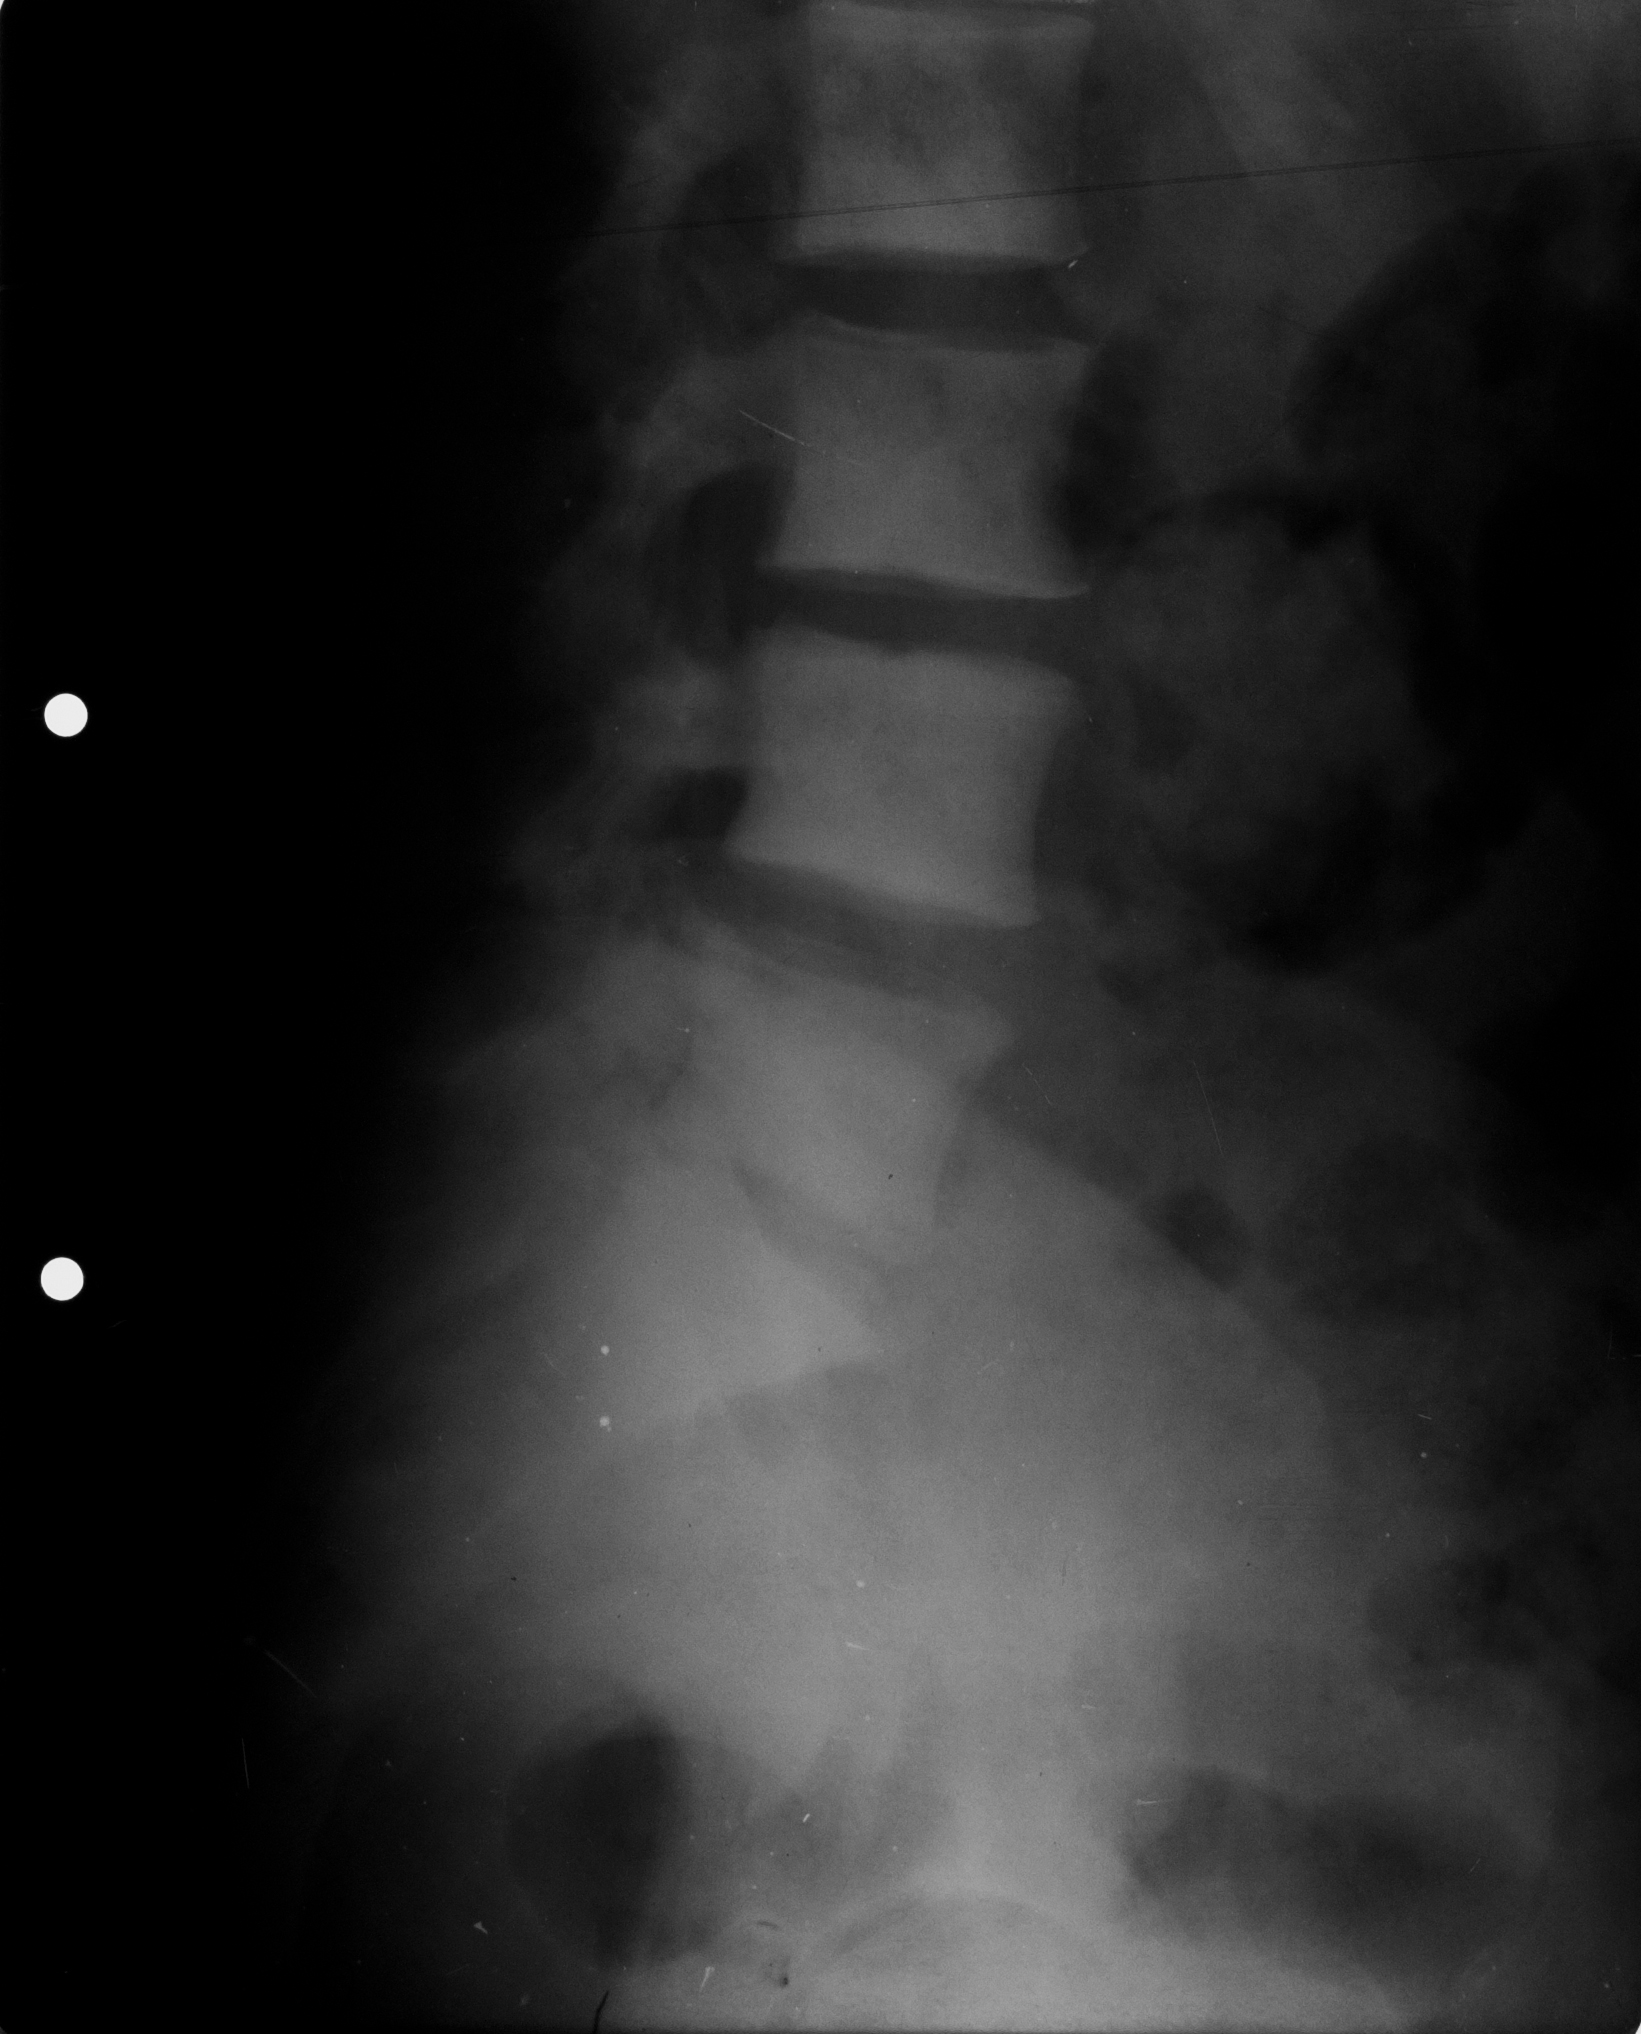

Cifoza rotunda, caracteristica persoanelor in varsta, datorata osteoporozei generalizate

- radiografie de coloana toracala, cu accentuarea cifozei toracale

- corpuri vertebrale mai putin opace decat ar trebui si avand forma trapezoidala, nu dreptunghiulara, cu tasare anterioara a acestor corpuri vertebrale